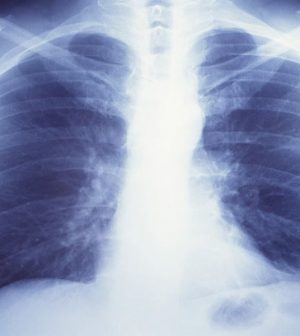

FRIDAY, Jan. 29, 2021 (HealthDay News) — Current and former smokers are at risk for a lung disease called pulmonary fibrosis, but many aren’t aware of the threat, the Pulmonary Fibrosis Foundation says.

There is no cure for the disease, which affects more than 200,000 Americans.